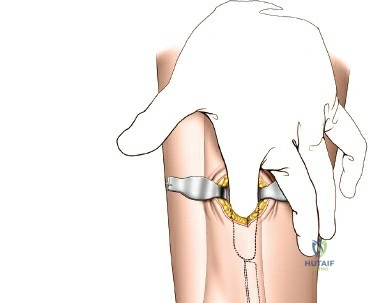

- Subcutaneous Tunnel Creation: After skin incisions, subcutaneous dissection is performed to elevate skin flaps minimally. A submuscular or subcutaneous tunnel is then created, connecting the proximal and distal incisions. This tunnel should be just wide enough to accommodate the plate. Blunt dissection (e.g., using a blunt elevator, specialized plate insertion guide, or fingers) is critical to preserve the periosteum overlying the fracture fragments, which maintains their blood supply and vitality.

- Protection of Neurovascular Structures: Meticulous care must be taken to identify and protect superficial peroneal nerve branches (anterolateral aspect), saphenous nerve and vein (anteromedial aspect), and deep peroneal nerve and anterior tibial vessels (anterior compartment).

- The chosen plate is carefully slid into the submuscular/subcutaneous tunnel created earlier, from either the proximal or distal incision.

- A plate inserter handle or targeting guide may be used to maneuver the plate and align it correctly on the bone surface.